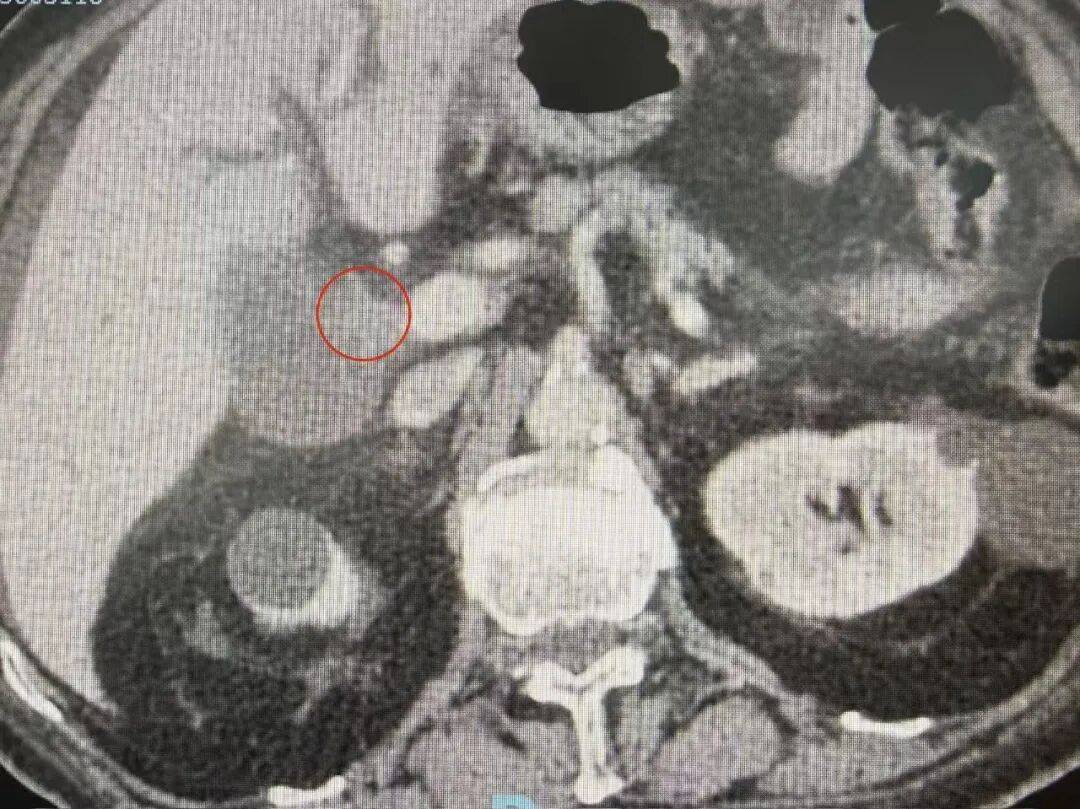

直到半个月前,老人因心脏病发作入住我院心血管内科,准备接受永久性心脏起搏器置入术。然而,术前常规检查时竟查出了“险情”。老人的肝功能指标严重异常,进一步影像学检查提示,肝门部存在占位性病变,高度怀疑是肝门部胆管恶性肿瘤。这一意外诊断让本就棘手的病情雪上加霜,也为后续诊疗出了一道难题。

图说 / 术前检查时发现肝门部胆管恶性肿瘤